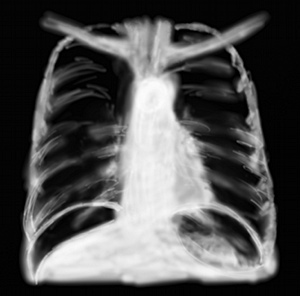

RP éventration diaphragmatique

Les anomalies du diaphragme se voient au bas d’un cliché thoracique.

Indirectes, c’est l’ascenscion de coupole quand un segment ou lobe de poumon se ratatine par atélectasie (cf embolie pulmonaire).

Directes, les tumeurs du diaphragme sont rares, elles se voient comme une opacité débordant la courbure à convexité supérieure. Les faiblesses de ce muscle plat sont plus fréquentes. La subtilité entre hernie et éventration diaphragmatique est dans le fait que l’éventration est une faiblesse musculaire (obèse, sujet âgé) et la hernie est plutôt traumatique par rupture.

Complète, on peut voir du contenu digestif (aérique pur, niveau) dans l’hémithorax (gauche le plus souvent) ou une coupole beaucoup plus haute que la normale. En cas de doute, la position d’une sonde gastrique à hauteur du thorax (alors qu’elle est bien positionnée dans l’estomac) signe le diagnostic.

Partielle c’est une opacité en partie floue, qui n’est pas dans la continuité de la coupole.

RP rupture diaphragmatique

La radiographie montre rarement un aspect fiable, c’est le scanner qui fait le diagnostic.